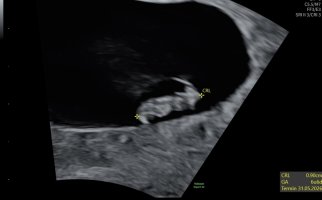

Nå skal de første på ultralyd, så tenkte det er hyggelig med en tråd hvor vi kan dele bilder

Ultralydbilder

Ok, så jeg er litt lettet og litt stresset. Graviditeten ligger på rett plass, inni livmor denne gangen , hurra! Men, jeg ble satt tilbake til 5+?. Gikk ikke an å se noe hjerteslag, men hun på sykehuset var positiv, og hun henviste meg til en ny time 17. oktober.

Fine hjerteslag og god bevegelse!

Fine hjerteslag og god bevegelse!